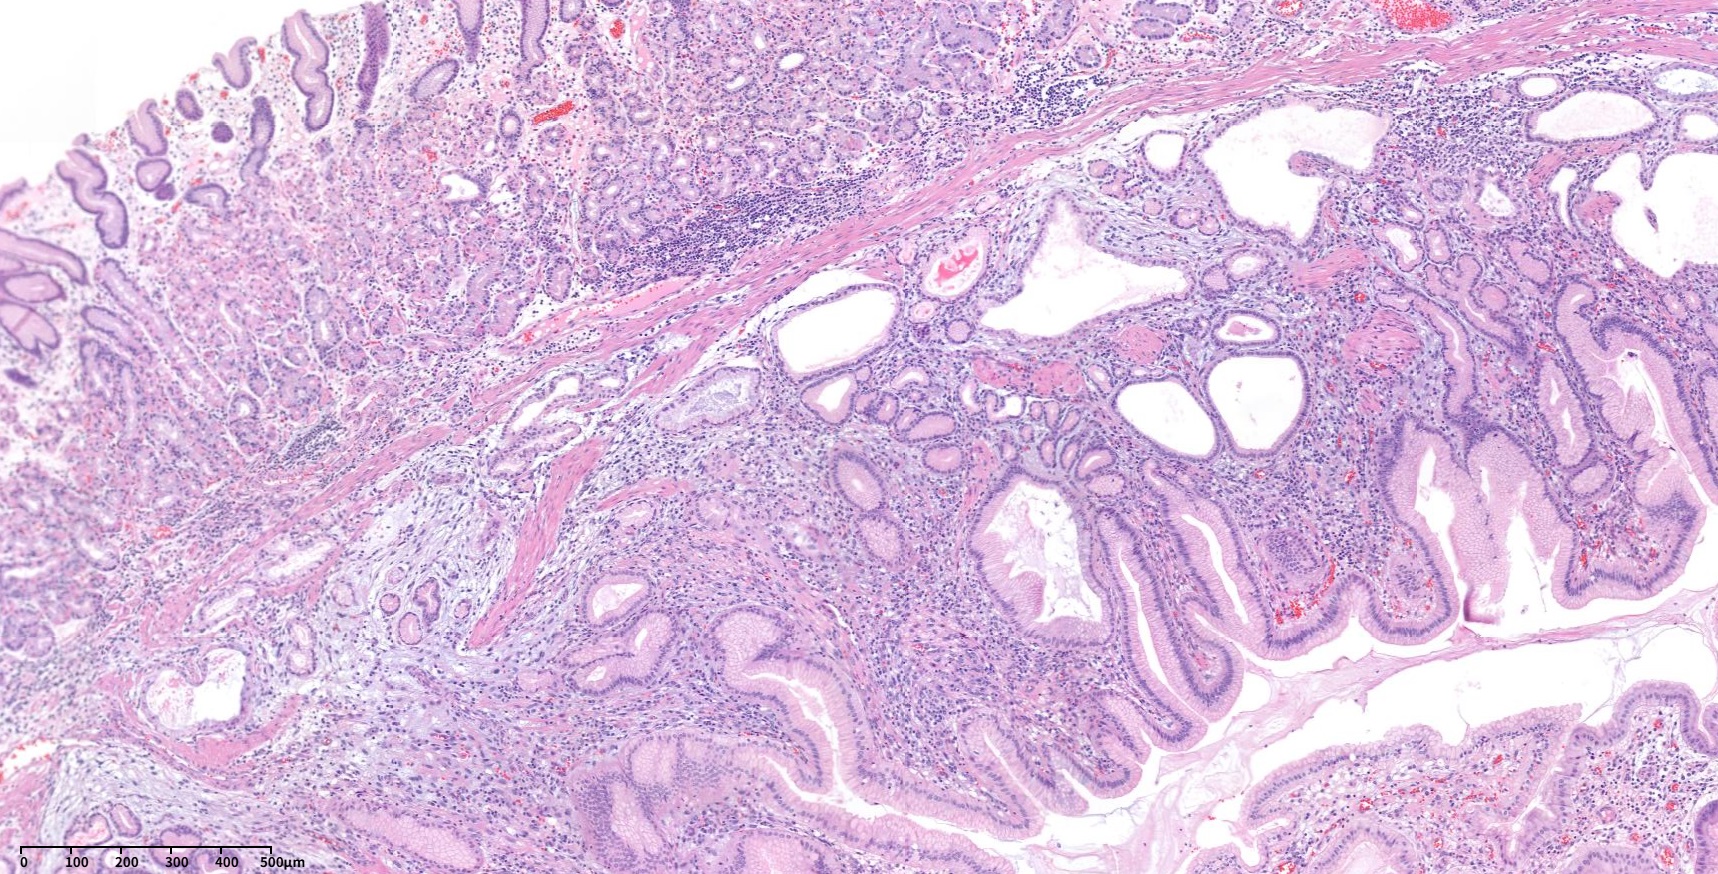

60¼¼ ³²¼ºÀÌ °Ç°­°ËÁø ³»½Ã°æ¿¡¼­ ¿ì¿¬È÷ ¹ß°ßµÈ À§ÀúºÎÀÇ 3cmÅ©±âÀÇ umbilicated ulcer¸¦ µ¿¹ÝÇÑ Á¡¸·ÇÏÁ¾¾ç ¼Ò°ßÀ¸·Î ÀǷڵǾú´Ù. ³»½Ã°æ °Ë»ç ´ç½Ã Á¶Á÷°Ë»ç ºÎÀ§ Áß ÇÑ °÷¿¡¼­ white thick mucinous materialÀÌ »ßÁ®³ª¿À´Â ¼Ò°ßÀÌ º¸¿´°í (»çÁø 1½Ã ¹æÇâ) ÂðµæÇÑ ´À³¦ÀÇ Á©¸®°°±âµµ ÇßÁö¸¸ Æ÷¼ÁÀ¸·Î ÀâÈ÷Áö´Â ¾Ê´Â´Ù´Â ¼Ò°ßÀÌ ±â¼úµÇ¾î ÀÖ¾ú´Ù. ¿ÜºÎ Á¶Á÷°Ë»ç °á°ú´Â stromal cell proliferation in lamina propria¿´°í ¾Ç¼º GIST (gastrointestinal stromal tumor) °¡´É¼ºÀÌ °í·ÁµÇ¾ú´Ù. ÀÇ·Ú ÈÄ ¿ÜºÎ ½½¶óÀ̵å ÀçÆÇµ¶ÇÑ ¼Ò°ßÀº Spindle cell tumor. differential diagnosis: GISTÀ̾ú´Ù. ³»½Ã°æ Àç°ËÀ» ÇÏ¿´°í À°¾È ¼Ò°ßÀº ºñ½ÁÇßÀ¸¸ç Á¶Á÷°Ë»ç Àç°ËÀº Chronic gastritis, active, with erosion, No definite submucosal tissue included·Î º¸°íµÇ¾úÀ¸¸ç DOG-1°ú C-KIT (CD 117)¿¡ ´ëÇÑ ¸é¿ªÇü±¤¿°»öÀº À½¼ºÀ̾ú´Ù. CT¸¦ ½ÃÇàÇÏ¿´À¸¸ç À§ÀúºÎ¿¡ ¾à 3 cmÀÇ endophytic mass°¡ ÀÖÀ¸¸ç central umbilicationÀÌ ÀÖ¾úÀ¸¸ç Á¤»ó mucosa·Î µ¤¿©ÀÖ¾î Á¡¸·ÇÏÁ¾¾çÀÇ °¡´É¼ºÀÌ ÀÖ´Â °ÍÀ¸·Î ÆÇµ¶µÇ¾ú´Ù. ºñ·Ï Á¶Á÷°Ë»ç¿¡¼­ È®ÀεÇÁö´Â ¾Ê¾ÒÀ¸³ª spindle cell proliferationÀÌ È®ÀÎµÈ ¹Ù ÀÖ°í ³»½Ã°æ À°¾È¼Ò°ß¿¡¼­ Áß¾ÓÀÇ Ç¥¸éÀÌ ºÒ±ÔÄ¢ÇÑ ÇÔ¸ôºÎ°¡ ÀÖ¾úÀ¸¹Ç·Î GISTÀÇ °¡´É¼ºÀ» °í·ÁÇÏ¿© ¿Ü°ú ÀÇ·ÚÇÏ¿© ½û±âÀýÁ¦¼úÀ» ÇÏ¿´´Ù. ÃÖÁ¾ º´¸® °á°ú´Â Herniated gastric mucosa with marked smooth muscle proliferation in submucosa, consistent with hamartomatous inverted polyp (1.7x1.6 cm)À̾úÀ¸¸ç desmin ¸é¿ªÇü±¤¿°»öÀº ¾ç¼ºÀ̾ú´Ù. À§ ¼Ó¸»¸² °ú¿ÀÁ¾¼º ¿ëÁ¾ (gastric inverted hamartomatous polyp, GIHP)Àº À§Á¡¸·ÇÏÃþ¿¡¼­ À§»ùÀÌ Áõ½ÄµÇ°í ³¶¼º È®ÀåÀ» º¸ÀÌ´Â °ÍÀ» Ư¡À¸·Î ÇÏ´Â ÁúȯÀÌ´Ù. º´¸®ÇÐÀûÀ¸·Î ÆòȰ±Ù Áõ½ÄÀ» º¸ÀÏ ¼ö ÀÖ´Ù. ÀϹÝÀûÀÎ °ú¿ÀÁ¾¼º ¿ëÁ¾ÀÌ ¿Ü¼ºÀå(exophytic growth)À» º¸ÀÌ´Â °Í¿¡ ºñÇÏ¿© GIHP´Â ³»¼ºÀå(endophytic growth)À» º¸ÀδÙ. ³»½Ã°æ ¼Ò°ß¿¡¼­ Ç¥¸éÀ¸·ÎºÎÅÍ ¿ìÀ¯°°Àº ¹Â½ÅÀÌ ¹èÃâµÉ ¼ö ÀÖ´Ù. ÃÊÀ½ÆÄ ³»½Ã°æ ¼Ò°ßÀº À̼Ҽº ÃéÀå Á¶Á÷°ú ±¸ºÐÀÌ ¾î·Æ´Ù. ¾à 20%ÀÇ ¾Ç¼ºÈ­ °¡´É¼ºÀÌ ÀÖÀ¸¹Ç·Î 2cm À̻󿡼­´Â ÀýÁ¦¼úÀ» ±ÇÇÑ´Ù.

Stomach, wedge resection: Herniated gastric mucosa with marked smooth muscle proliferation in submucosa, consistent with hamartomatous inverted polyp (1.7x1.6 cm)

GIHPs are a distinct entity characterized by submucosal growth of hypertrophic glands with cystic dilatation. They are distinct from the other types of hamartomatous polyps, which have an exophytic configuration contrary to the endophytic nature of these polyps. On endoscopic examination, these are reported as solitary submucosal masses. On endoscopy, extrusion of milky mucinous material from the surface of the lesion and calcifications from the biopsy site may provide a clue to diagnosis. On histology, there is cystic proliferation of glands, which may be accompanied by smooth muscle proliferation, and formation of ectopic duct-like structures has also been reported. In addition, fibroblastic and neural proliferation may also be seen with glandular elements. Diagnosis of GIHP is difficult without pathologic examination and may mimic ectopic pancreas on endoscopy and endosonography. Certain features have been suggested on endoscopic ultrasound imaging, such as hyperechoic lesions with hypoechoic spots, which might be suggestive of GIHPs. En bloc removal is recommended in lesions >2 cm due to the associated malignant risk (up to 20% risk of malignancy). Though it is rare, Hirasaki et al have reported a case of GHIP associated with signet ring cell carcinoma.

Wedge resection: herniated gastric mucosa in the submucosa with cystic dilatation

Herniated gastric mucosa in the submucosa